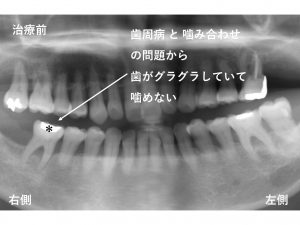

初診時が以下です。

下顎右側の一番奥歯に問題がありました。

*印の歯です。

歯周病 と 噛み合わせ の問題から

歯がグラグラしていて噛めない

とのことです。